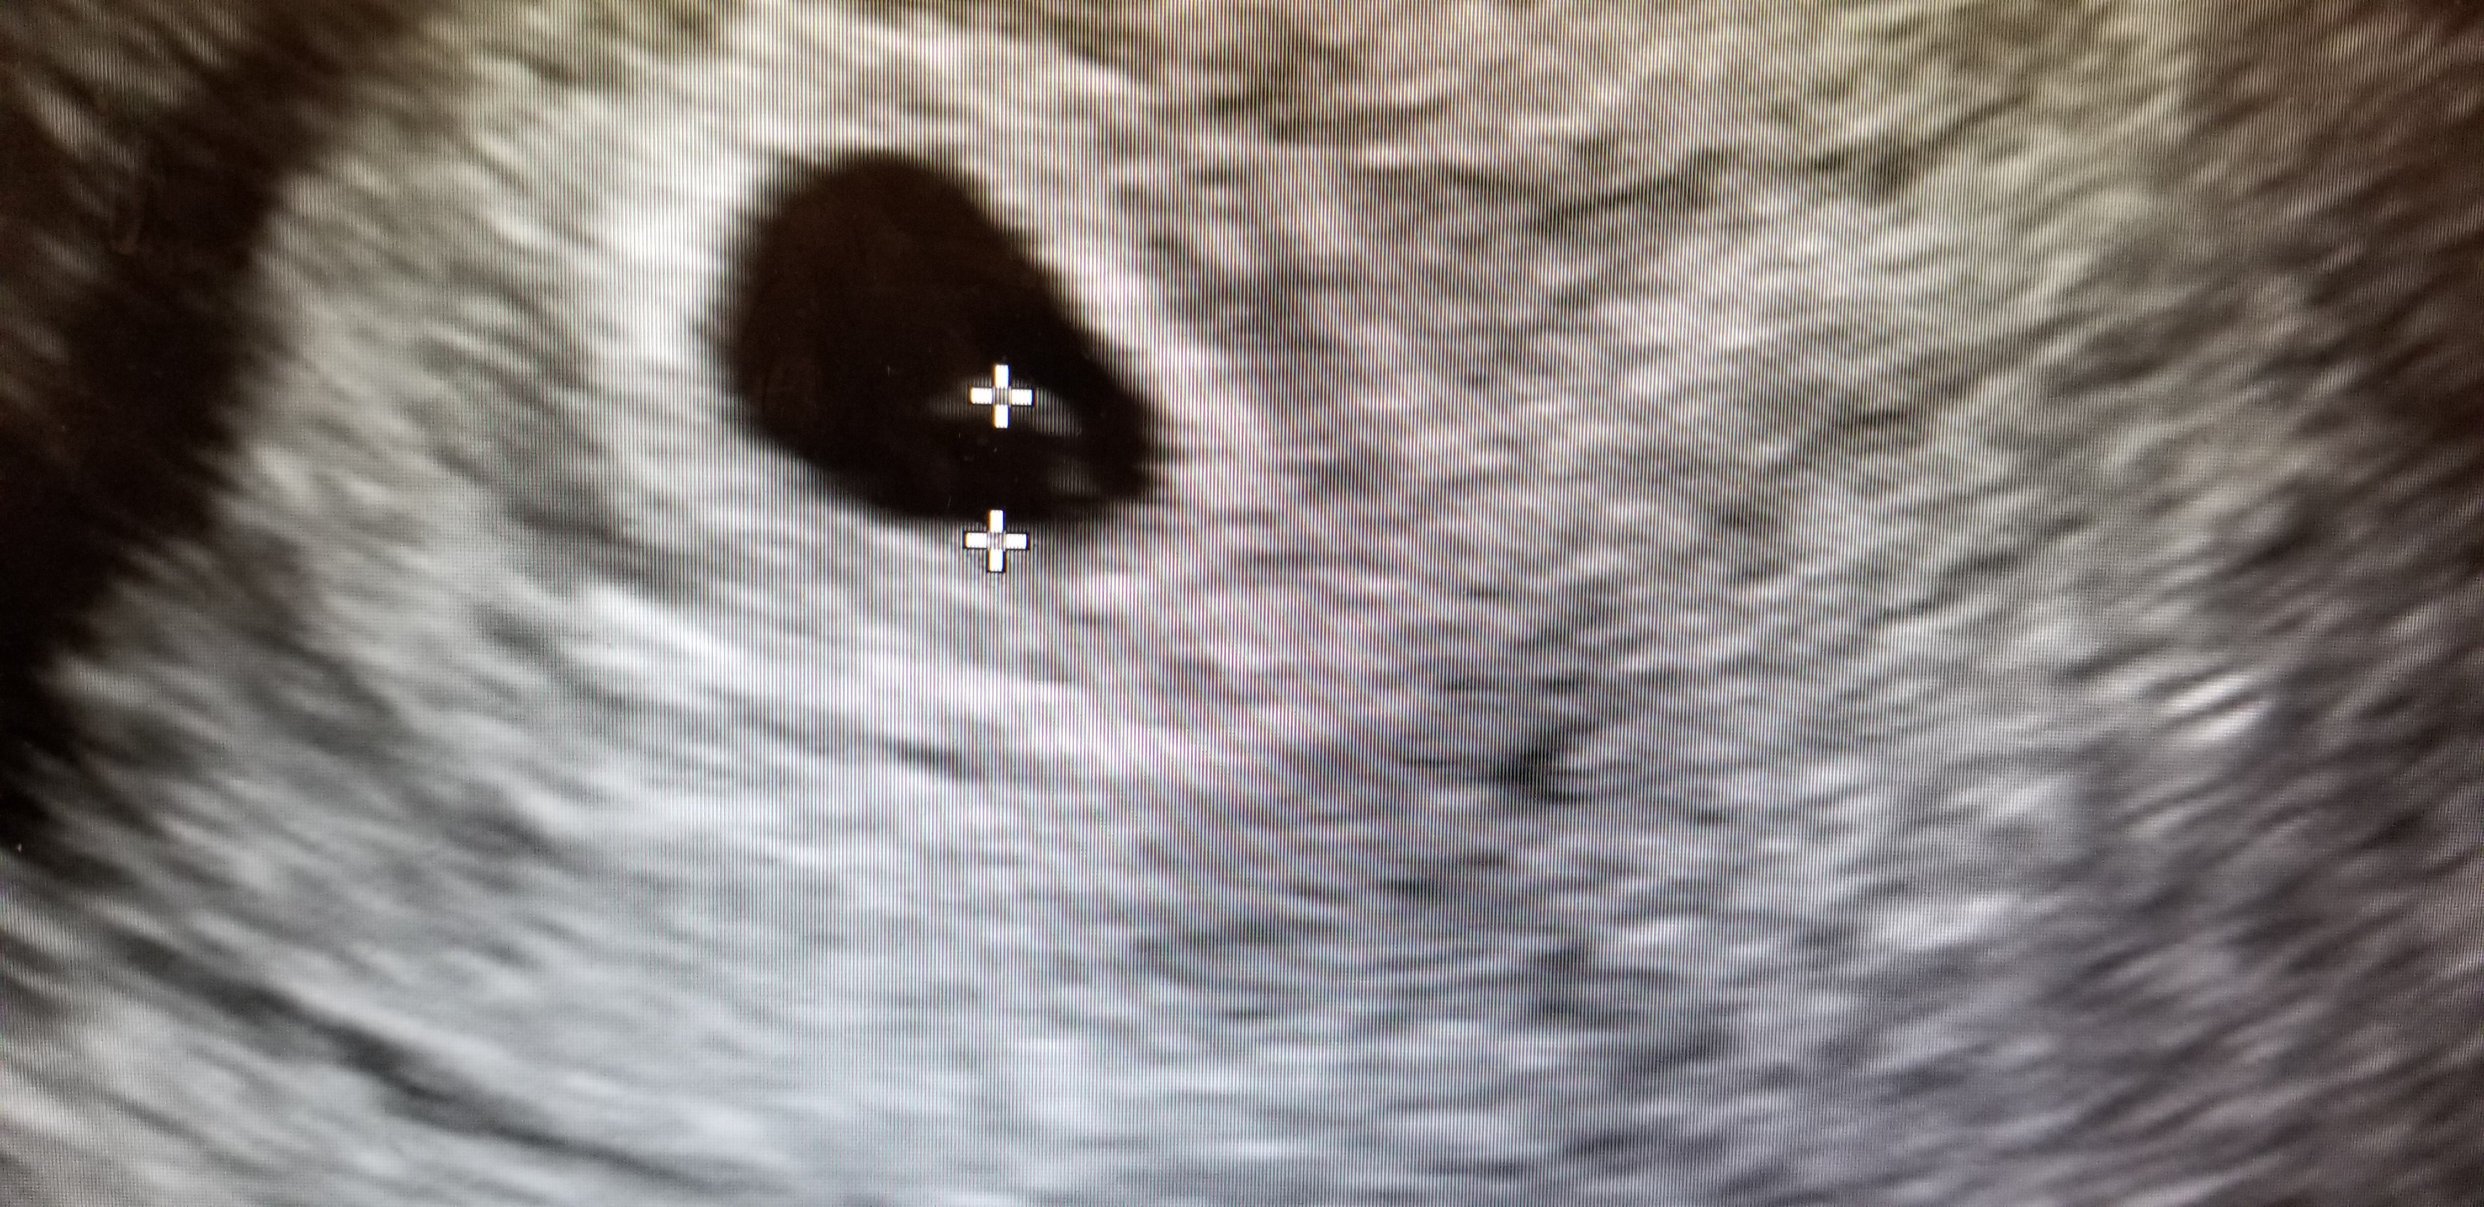

If you see the two little dots in the black of my uterus, you'll realize there's twins in there! As of right now though, they're looking to be monoamniotic-monochorionic twins. This means they share a placenta and an amniotic sac, or they likely will if one of the twins doesn't get reabsorbed. However, since they both had their own yolk right now, it's poooooooosible (but not likely) that they'll each develop their own amniotic sacs. The result is either going to be that one of the twins will be lost or I will have a very high risk mo-mo pregnancy.